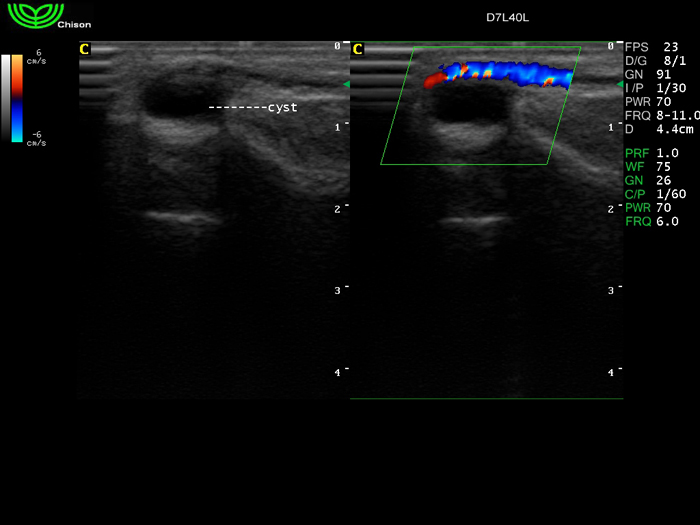

D7L40L 7.5МГц, линейный.

4.0МГц – 13.0 МГц. Применения: грудь, малые органы, нервы, сосуды, венозная катетеризация, мышцы и скелет, управление биопсией. |